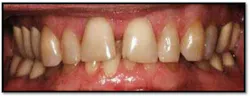

UR/LR Pre TxThe tissues around the posterior crowns are almost bluish in color(above left)UL/LL Pre Tx:

Pockets 4-6mm, gen posterior BOP